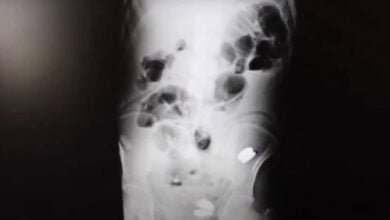

انتشال 233 قطعة نقدية وبطارية ومسامير من بطن رجل

إعداد: مصطفى الزعبي أخرج الأطباء 233 قطعة نقدية وبطارية ومسامير من معدة رجل تركي (35 عاماً)، عندما نقل إلى المستشفى…